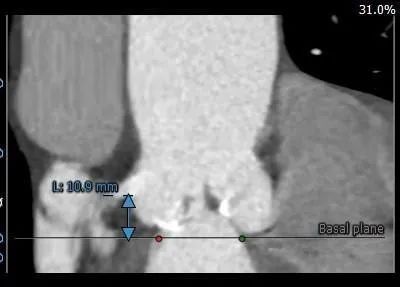

主动脉根部测量:

瓣膜第一次释放到工作位置偏高

位置偏深

第三次零位定位

第三次释放位置理想